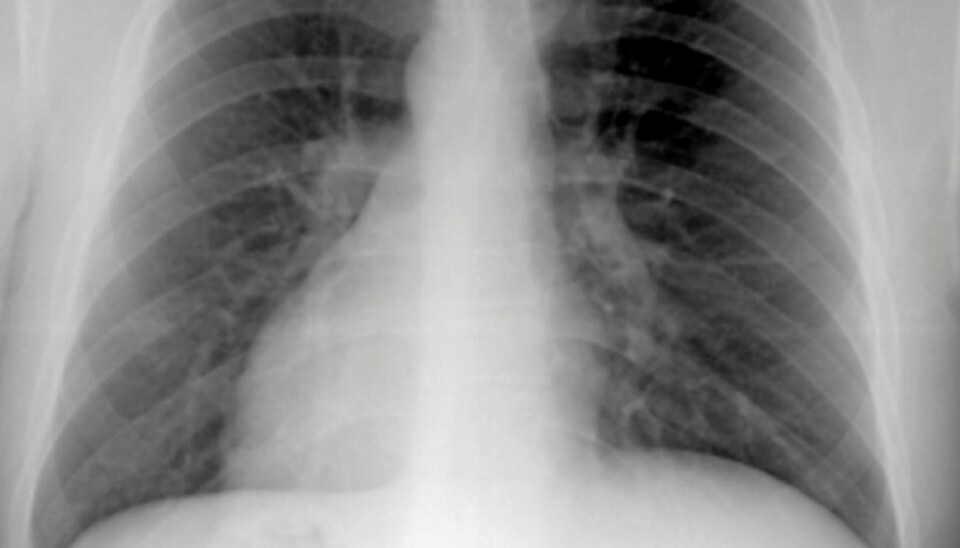

DØDELIG: KOLS er nå den fjerde vanligste dødsårsaken i vestlige land. Mange vet ikke at de har det.

KOLS er en sterkt røykerelatert sykdom. Den fører blant annet til en gradvis og stadig mer plagsom og invalidiserende svekkelse av lungefunksjonen.

KOLS gir økende uførhet og er nå er den fjerde vanligste dødsårsaken i vestlige land. Kanskje kan denne trenden snu med bedre medisinering.